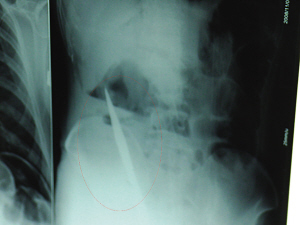

X光片上,尖刀清晰可見。

從男子體內取出的尖刀足足有19厘米長。

6日上午,記者在徐州礦務集團總醫院重癥監護室見到了這名男子,目前他雖然已經恢復了意識,但還不能開口說話,需要呼吸機輔助呼吸。據醫生介紹,4日中午12時左右,這名男子因服毒輕生被緊急送到醫院進行搶救,之前,這名男子已經在當地鄉鎮醫院進行了近20小時的治療,但效果不佳。“病人被轉院到礦總院時已神志不清,血壓極低,處于休克狀態。”救護人員給男子洗胃、初步處理以后,發現男子呼吸急促,于是趕緊給他拍片檢查。結果讓所有的醫生大吃一驚,竟有一把尖狀異物橫在該男子腹腔內!當天下午5時30分,輕生男子被推上了手術臺。經過40多分鐘的手術,該男子腹腔被打開,手術醫生發現,男子體內的金屬狀異物竟然是一把長19厘米的尖刀!

醫生告訴記者,手術后,醫生在病人身上并未發現刀痕,最后,經過檢查發現,在該男子直腸處找到穿孔。醫生從醫學角度分析后認為,這把尖刀應該是從肛門插入直腸的。醫生說,因為病人搶救及時,尖刀并未傷及要害,所以暫時保住了性命,但后期可能會出現腹腔感染、AIDS、器官衰竭等多種并發癥。